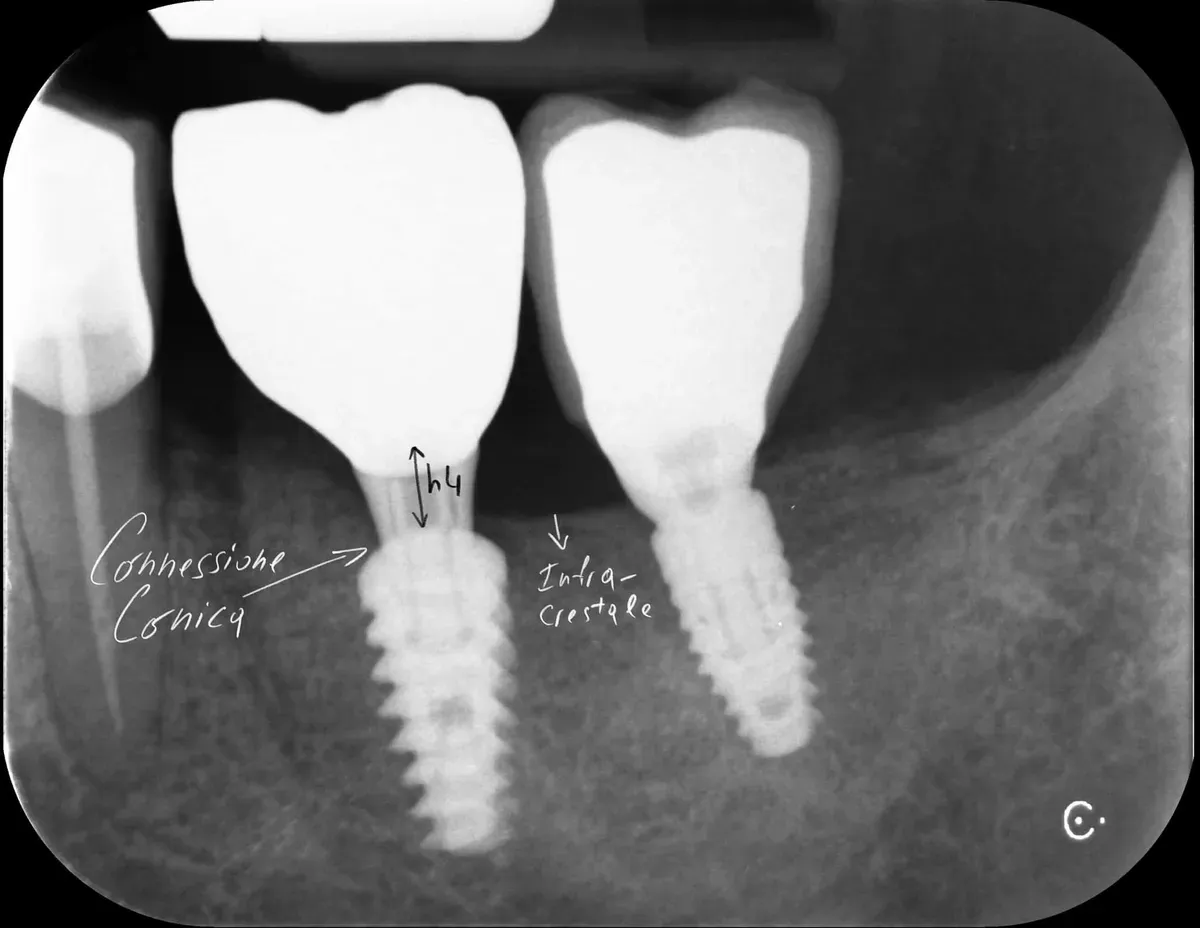

Sull’altezza: la review di Muñoz e collaboratori (https://doi.org/10.1111/clr.14025), basata solo su RCT, ha identificato una soglia di 2 mm. Abutment alti almeno 2 mm svolgono un ruolo protettivo contro la perdita ossea marginale, permettendo la formazione dell’adesione mucosale sovracrestale. Questo effetto appare indipendente dallo spessore dei tessuti molli, anche se in caso di tessuti sottili è importante posizionare gli impianti sottocrestali (o meglio, “infracrestali”) per consentire la formazione del complesso mucosale sovracrestale.

La regola dei 4mm di Linkevičius ci viene in aiuto per stabilire la posizione verticale che protegge l’impianto dal riassorbimento osseo, sempre nel caso di connessioni affidabili dal punto di vista batteriologico. Nelle prossime immagini, dei monconi protesici relativamente lunghi su impianti a connessione conica, testimoniano l’ottimo risultato reale di questo concetto, con impianti perfettamente integrati e privi di infiltrazione infiammatoria, anche in condizioni ossee impegnative.

Per concludere il confronto tra le varie connessioni, l’immagine che segue è una radiografia con due impianti affiancati: un tissue-level ben posizionato fatto da un collega anni addietro e un impianto a connessione conica in posizione infracrestale con abutment della corretta lunghezza per il caso. Il secondo è un mio caso. È interessante notare come il cono dello spazio biologico sia identico. Se ben posizionati, tutti gli impianti funzionano egregiamente (l’impianto più vecchio inizia a soffrire un pochino, ma questa è un’altra storia).